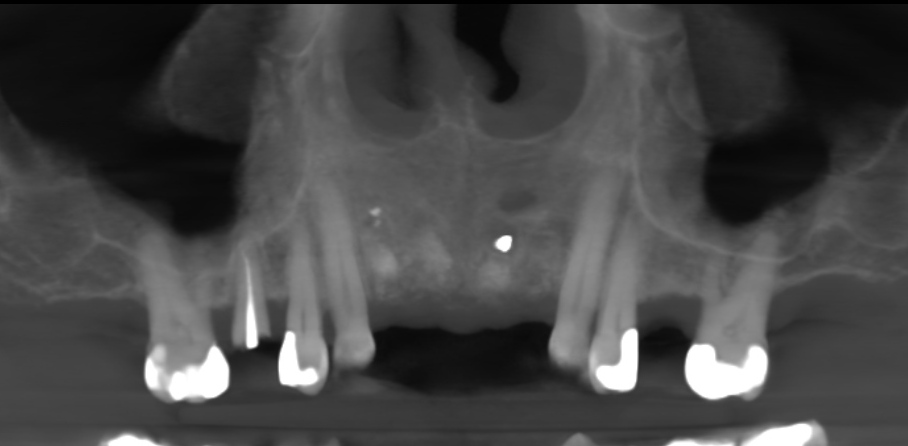

The first step was to obtain a CBCT scan of the maxillary arch, which revealed periapical pathology in teeth #12-22 (Figs. 2 & 3). Furthermore, tooth #21 exhibited significant loss of buccal bone, and a small piece of amalgam was identified in the bone near tooth #21. After a thorough analysis of the radiographic findings, a treatment plan was established to extract teeth #12-22 and perform ridge preservation to reduce bone loss in the extraction sites.

Fig. 2: Initial CBCT scan of the maxillary arch.

Fig. 3: Initial CBCT scan. Coronal view of tooth #21 showing buccal bone loss.